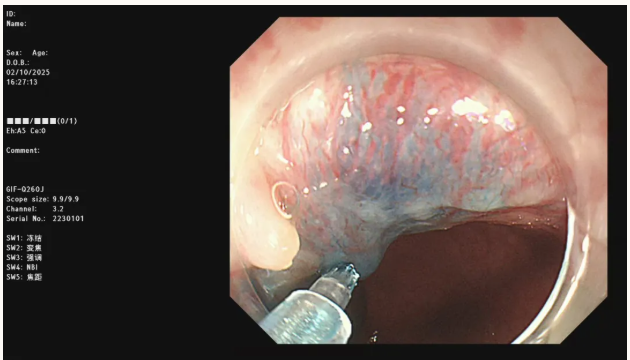

食管胃底曲张静脉内镜下硬化治疗

一例食管胃静脉曲张破裂出血治疗